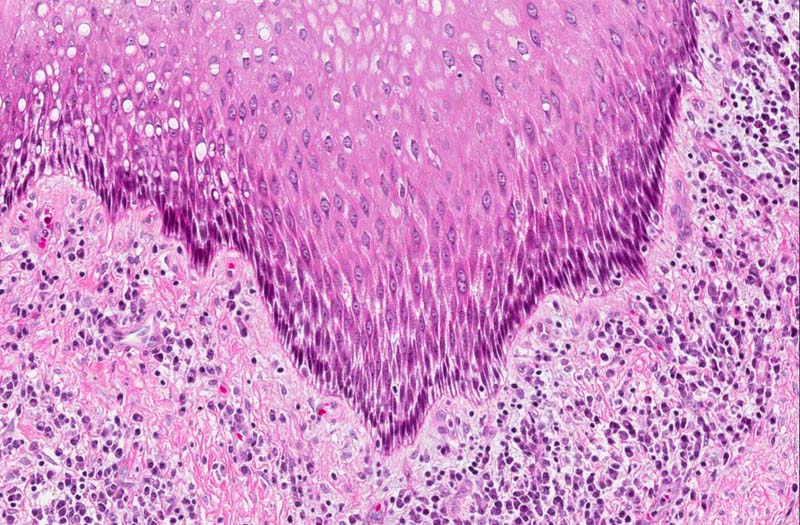

Hematoxylin & eosin

Area 2: In this area, there is thickening of the epidermis. At the same time, this area is also tangentially sectioned which lead to elongation of the nuclei and cells. Note that the degree of chronic inflammatory cell infiltration is more intense in comparison from that of area 1.

• In some areas, there is hyperplasia of the epithelium (area 2) but no dysplastic changes are noted.

• The basal layer of epithelial cells is composed of hyperchromatic cuboidal to columnar-appearing cells with a tendency for nuclear palisading (area 1 and 2).